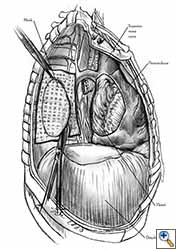

The pleural flap is easy to harvest but is not a strong material. Pedicled pericardial fat is frequently used to cover the bronchial stump after pneumonectomy and simultaneously for pericardioplasty. Because it is not a strong material, cardiac herniation after pericardial reconstruction with mediastinal vascularized fat pad has been reported [3]. Fascia lata is efficient in terms of its strength, but using it requires anticipation of the pericardial reconstruction and the preparation of an additional operative field and an additional incision in the thigh region [1-3]. Pericardial reconstruction using a diaphragmatic patch (Figures 6a, 6b) requires careful harvesting of the graft to preserve its vascularisation from the phrenic arterial neurovascular trunk. The site of the diaphragmatic resection must be closed after reconstruction. The diaphragmatic patch is strong and elastic and it can also be used to cover the bronchial stump after pneumonectomy or to wrap the tracheo-bronchial anastomosis after sleeve pneumonectomy. Another potential advantage is the plication of the diaphragm at the site of its resection, which can prevent postoperative paradoxical diaphragmatic movement in patients with phrenic nerve resection for tumor involvement [8]. The main advantage of using autologous materials in pericardial reconstructions is that the material is well tolerated, resistant to infection, and free of cost.

Video 1 depicts a pericardial reconstruction with Marlex after a right completion pneumonectomy with pericardiectomy for lung adenocarcinoma (see also Figure 1). The technique of pericardial reconstruction after the resection of invasive mediastinal tumours is illustrated in Figures 8a-c). Video 2 depicts a pericardial reconstruction with Mersilene mesh after the resection of a malignant thymoma invading the anterior pericardium (see also Figure 4b). The technique of right pericardial reconstruction after extrapleural pneumonectomy is illustrated in Figures 9a and 9b). Video 3 depicts a pericardial reconstruction using Gore-Tex Dual Mesh after a left extrapleural pneumonectomy (see also Figure 3). Care must be taken to prevent constriction (Figure 10).

- The pericardium must be reconstructed in a geometric, tridimensional fashion to avoid constriction (Figures 10a, 10b).

| Figure 10a: Concept of geometric pericardial reconstruction. | Figure 10b: Non-geometric pericardial reconstruction can lead to cardiac tamponade. |